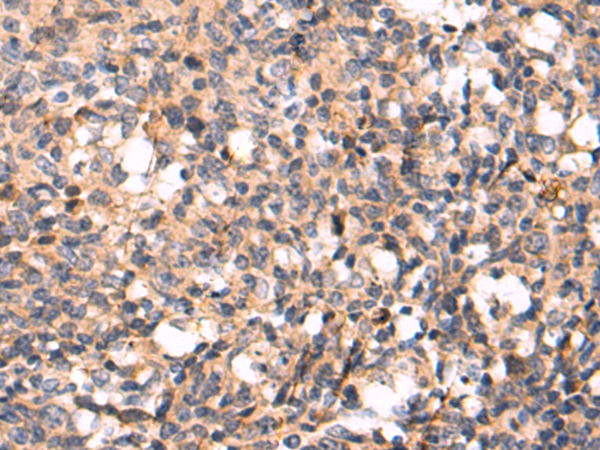

分类: 科研抗体货号: P07181别名: CMM3; PSK-J3应用: WB,IHC反应种属: Human, Mouse, Rat